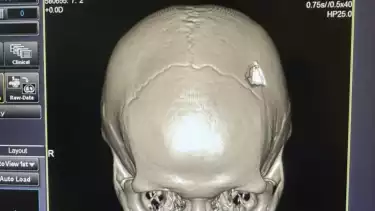

Cedera di Kepala Korban.

Medan, tvOnenews.com - Seorang pengunjung hotel menjadi korban dugaan pengeroyokan di Halaman Hotel Grand Central Premier, Jalan Merak Jingga, Medan, Sabtu (30/9/2023) dini hari. Akibatnya korban, Hendrik Ganie mengalami tempurung kepala pecah dan pembekuan darah di bagian paru-paru.

Menurut dia, akibat penyerangan itu, Hendrik Ganie mengalami tulang kepala retak dan paru-paru mengalami pembekuan darah.